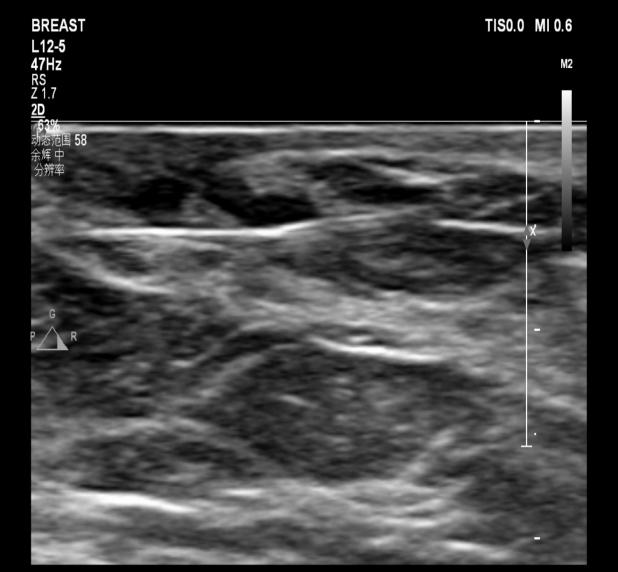

67岁的石女士(化名)在体检时发现了 “乳腺结节”,随后前来我院门诊就诊。经过超声检查,显示其左侧乳腺乳晕后方存在一枚实性结节,大小约为6×4mm,同时伴有局部乳导管的扩张情况。而超声造影结果表明,该结节呈现出快速高增强,且增强范围与二维图像保持一致,其BI-RADS分类为4a类,提示有导管内乳头状瘤的可能性。

在手术过程中快速捕获微小乳腺结节并实施完整切除是一项挑战。为了能够实现精准微创诊疗,我院普外科和超声科的医生们经过仔细讨论后,决定在术前对石女士的这枚乳腺小结节实施超声引导下定位针置入术。

超声引导下定位针置入术

超声引导下定位针置入术是对不可触及的可疑恶性的微小乳腺结节,利用一根纤细、尖端带钩的穿刺针,在超声实时动态监测下,经皮穿入结节内,释放穿刺针内的倒钩,钩住病灶,轻退穿刺针,将倒钩留于结节内,再将连于倒钩的导丝固定于体表。外科手术时,医生顺着导丝便能轻松捕获结节。

目前,我院超声科已常规开展此项技术。最终,石女士的结节通过手术被快速完整切除,病理诊断为导管内乳头状瘤。